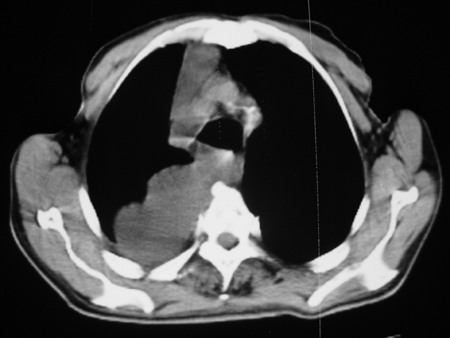

男77岁,胸痛就诊

右侧胸腔积液,部分包裹,右下肺膨胀不全,右下肺感染。

考虑右肺门占位并下叶不张 右胸包裹积液

右侧胸腔积液,部分包裹,右下肺膨胀不全

右肺中叶及下叶炎症并胸腔积液(部分包裹),建议抽液后复查ct除外占位。